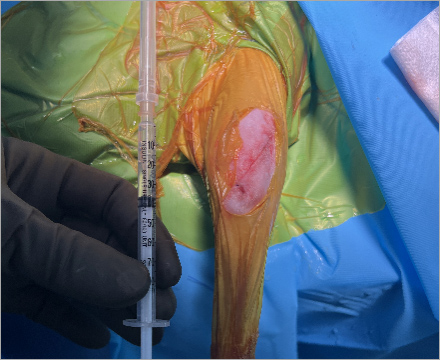

수술 중 율무는 절개도 최소화했고 출혈도 거의 없었으며 혈압과 맥박도 안정적이었다고 들었습니다.

근육・힘줄을 최대한 보존하는 최소 침습 TPLO 수술 시행하며 관절경을 통해 관절을 열지 않고 수술 진행하기때문에 환자의 통증을 최소화합니다.

최소절개 TPLO 수술

예은동물의료센터에서는 근육・힘줄을 최대한 보존하는 최소 침습 TPLO 수술 시행하며

관절경을 통해 관절을 열지 않고 수술을 진행하기때문에 환자의 통증을 최소화합니다.